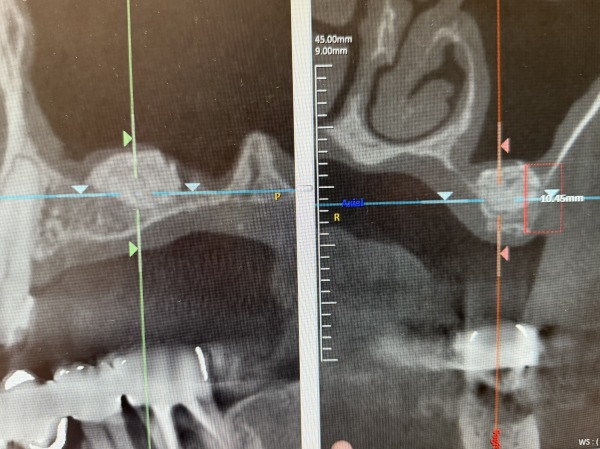

まずはCTを撮影し、インプラントができる状態であるかどうか診断を行いました。

こちらがCTでの診断画像(お顔を横から見ている状態)になります。

左上4番目はある程度の骨量があり、ソケットリフトという方法を用いてインプラント処置が可能と判断できました。

しかし、左上5番目は骨の厚さが3mm弱と薄く、この状態では噛む力に耐えられるインプラントの固定が得られず、サイナスリフト(上顎洞挙上術)という骨を作る特殊な処置を行った後にインプラント治療を行っていくことが必要と診断しました。

こちらがお顔を前から見ている状態の画像になります。インプラントを支える骨が少ないのが分かるかと思います。